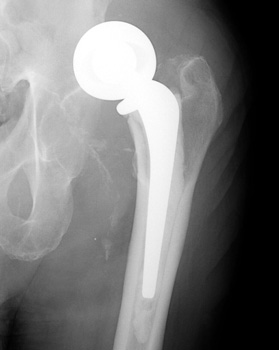

Dislocated femoral component secondary to steep acetabular cup

inclination, pre and post revision. Note constraining ring about femoral head,

which helps maintain head in cup